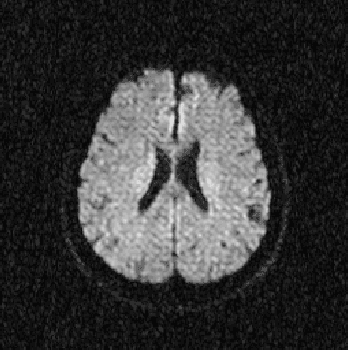

Abstract:Multispectral image analysis is a relatively promising field of research with applications in several areas, such as medical imaging and satellite monitoring. A considerable number of current methods of analysis are based on parametric statistics. Alternatively, some methods in Computational Intelligence are inspired by biology and other sciences. Here we claim that Philosophy can be also considered as a source of inspiration. This work proposes the Objective Dialectical Method (ODM): a method for classification based on the Philosophy of Praxis. ODM is instrumental in assembling evolvable mathematical tools to analyze multispectral images. In the case study described in this paper, multispectral images are composed of diffusion-weighted (DW) magnetic resonance (MR) images. The results are compared to ground-truth images produced by polynomial networks using a morphological similarity index. The classification results are used to improve the usual analysis of the apparent diffusion coefficient map. Such results proved that gray and white matter can be distinguished in DW-MR multispectral analysis and, consequently, DW-MR images can also be used to furnish anatomical information.

Abstract:The unsupervised classification has a very important role in the analysis of multispectral images, given its ability to assist the extraction of a priori knowledge of images. Algorithms like k-means and fuzzy c-means has long been used in this task. Computational Intelligence has proven to be an important field to assist in building classifiers optimized according to the quality of the grouping of classes and the evaluation of the quality of vector quantization. Several studies have shown that Philosophy, especially the Dialectical Method, has served as an important inspiration for the construction of new computational methods. This paper presents an evaluation of four methods based on the Dialectics: the Objective Dialectical Classifier and the Dialectical Optimization Method adapted to build a version of k-means with optimal quality indices; each of them is presented in two versions: a canonical version and another version obtained by applying the Principle of Maximum Entropy. These methods were compared to k-means, fuzzy c-means and Kohonen's self-organizing maps. The results showed that the methods based on Dialectics are robust to noise, and quantization can achieve results as good as those obtained with the Kohonen map, considered an optimal quantizer.